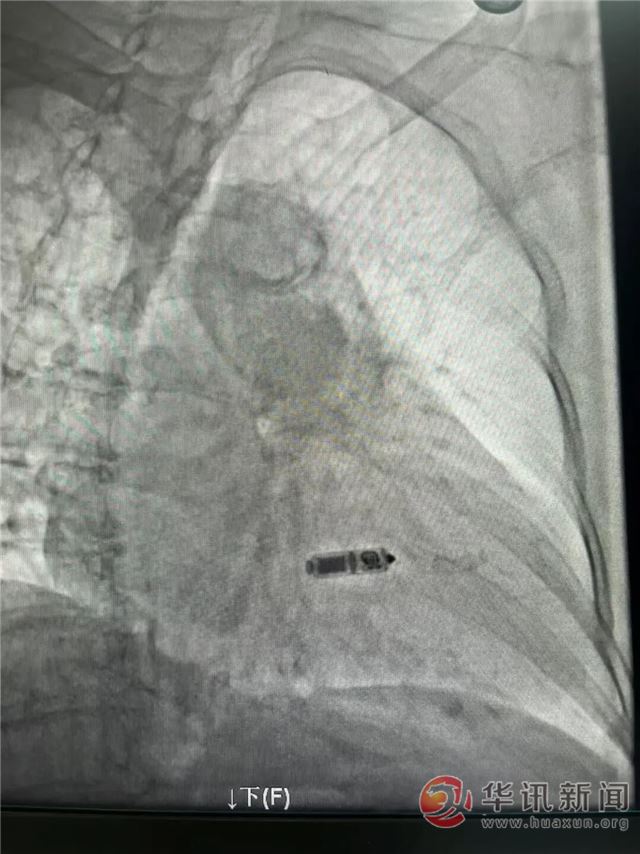

手术当日,王俊莉主任带领电生理团队成员在介入导管室紧密配合下,手术紧张而有序地展开。凭借丰富的手术经验和娴熟的导管操控技术,术者通过递送系统将微小的起搏器精准地送至患者右心室的中位间隔部。术中反复测试各项参数均表现优异,心房感知良好,实现了稳定的房室同步收缩。整个手术时长短,出血量极少。患者术后感觉良好,困扰多日的头晕症状消失,对治疗效果非常满意。

起搏器仅如一粒维生素胶囊大小,重量约2克,通过股静脉穿刺,直接植入在患者右心室及心房感知位点,避免了传统起搏器在胸前皮下制作囊袋及植入电极导线所带来的创伤、感染、导线脱位、断裂、静脉血栓形成等与导线相关的并发症风险。